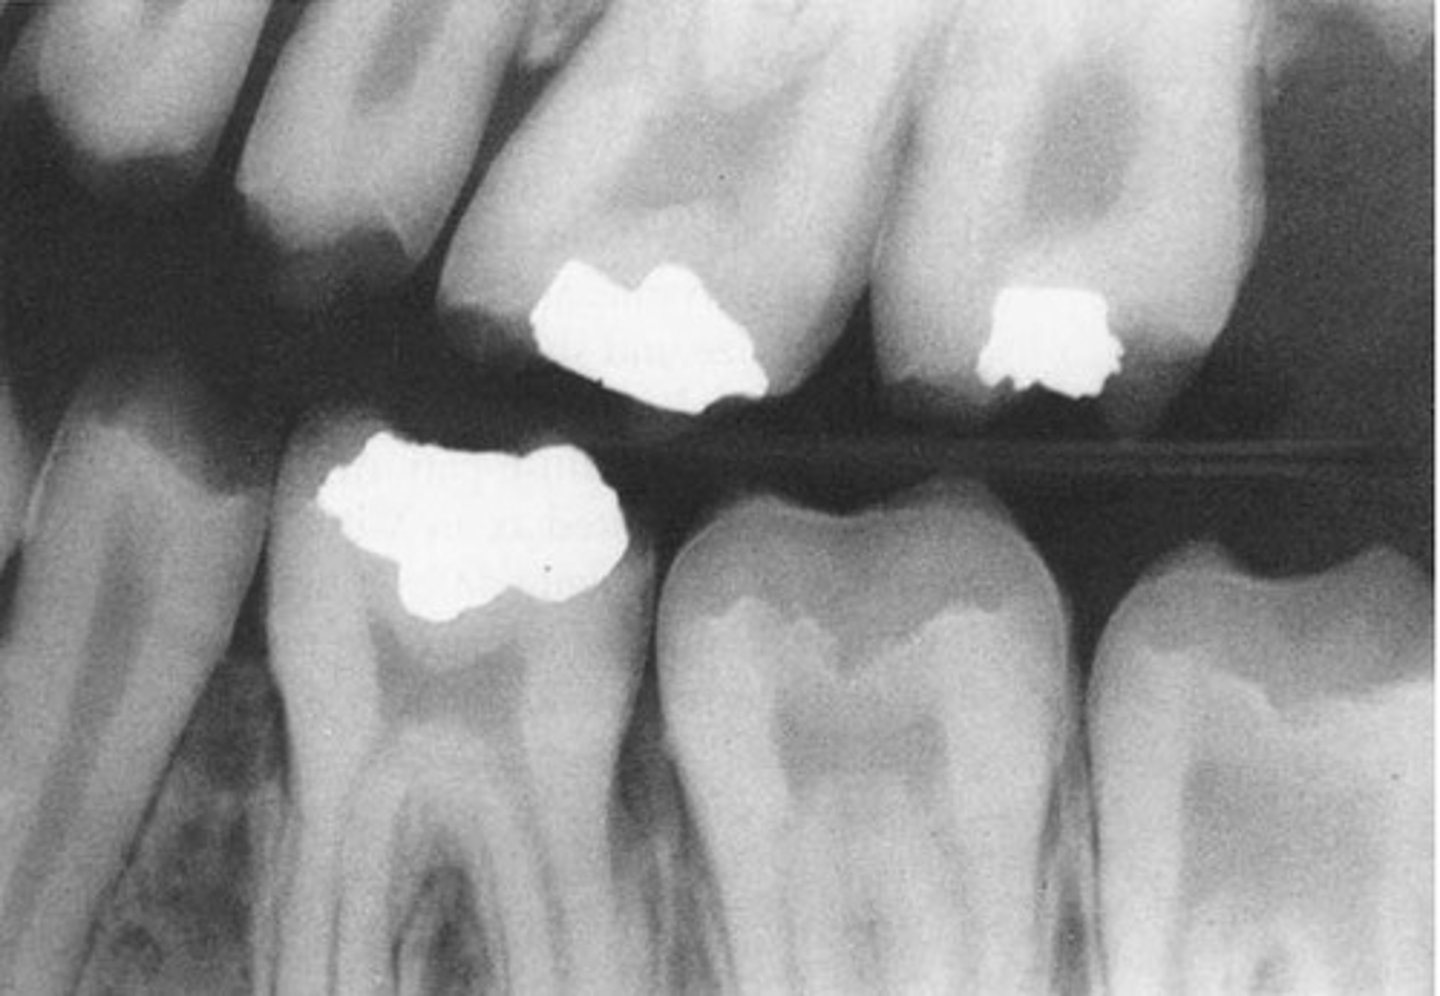

BW xray of a tooth with an amalgam and patient complained of pain when provoked by hot or cold. Why?

Deep amalgam filling

Multiple questions about eruption and looking at BW to see if its normal

STUDY ERUPTION TIMES!